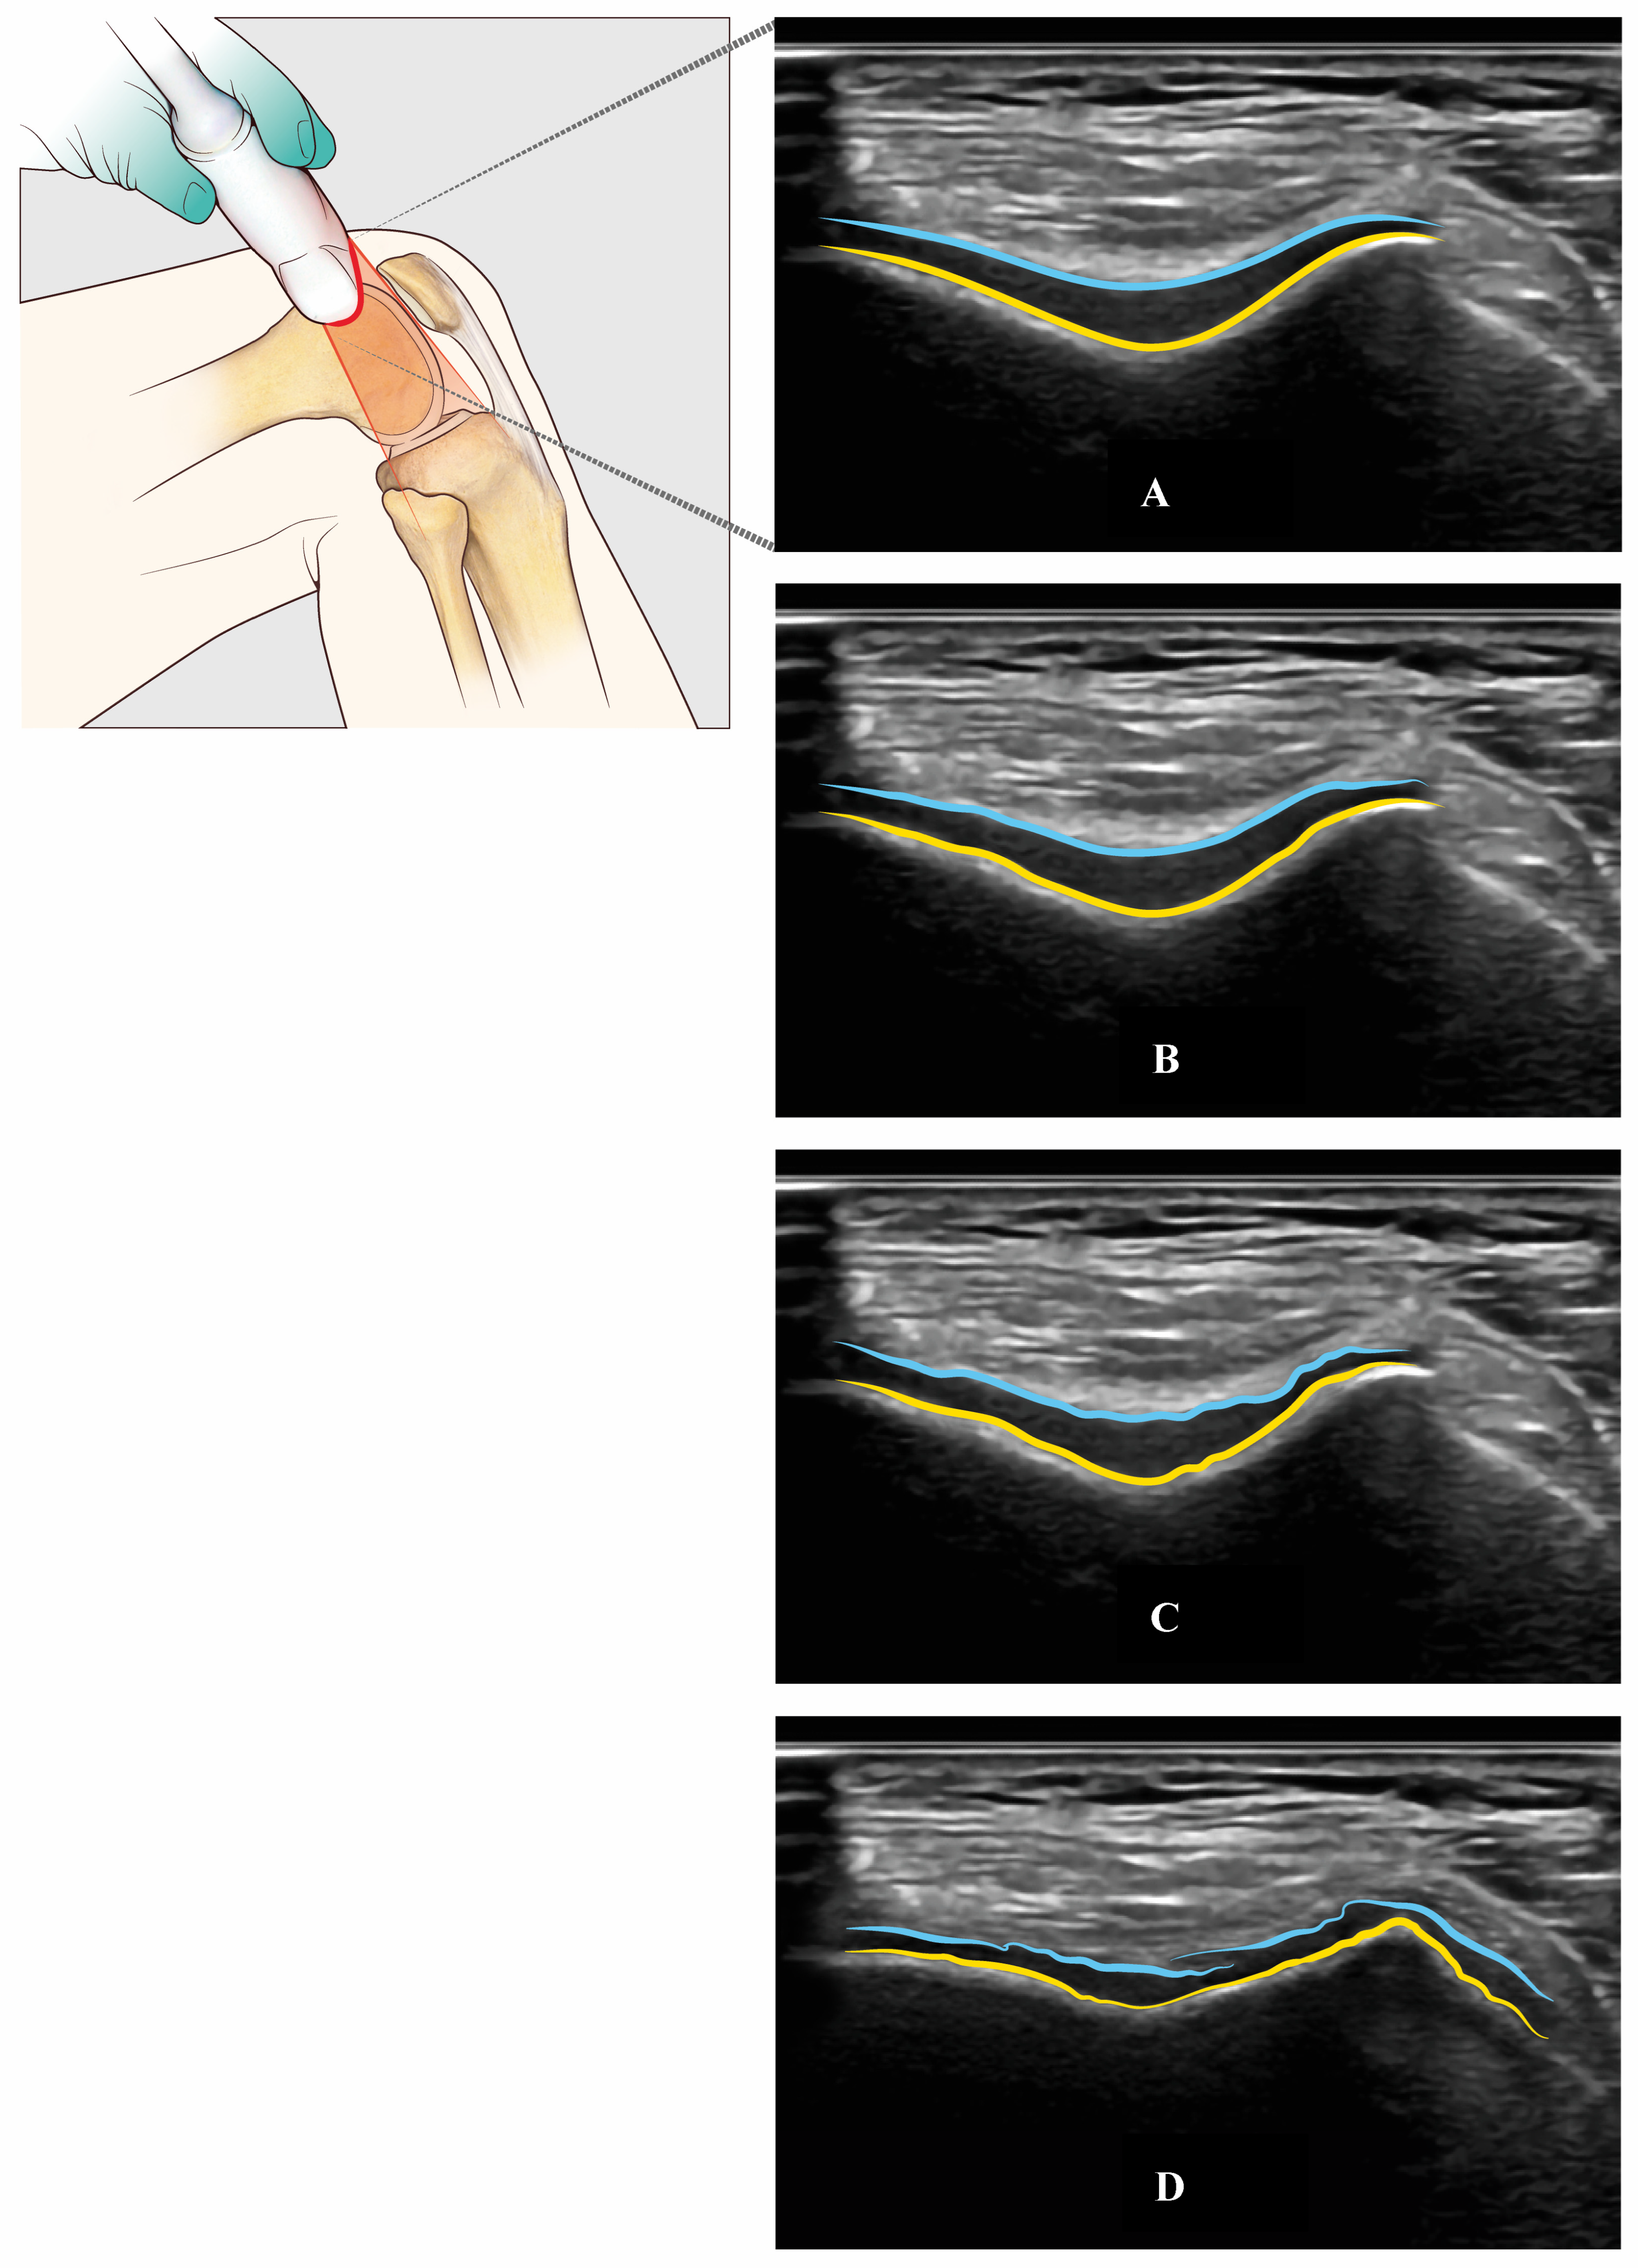

A US’s capability of assessing articular cartilage is somewhat limited and not yet fully explored. Specifically, a US provides only a restricted view of the femoral condylar cartilage, depending on patellar position, size, and morphology. On the contrary, a US is able to view all the trochlear femur cartilage through a suprapatellar view with the knee in maximal flexion (Figure 6).

Figure 6.

Trochlear femur’s cartilage assessed with US through an axial suprapatellar view with a flexion of the knee (light blue, superficial layer of the cartilage—yellow, cortical bone of the trochlear groove): Normal cartilage (Panel A), mild (Panel B), moderate (Panel C), and severe (Panel D) cartilage damage.

To address this limitation, Kauppinen et al. [69] conducted a study involving 20 healthy knees, utilizing both US and 0.6 mm isotropic MRI with a 90-degree flexed knee to evaluate the ability of US to visualize femoral articular cartilage. Their findings suggested that up to two-thirds of the articular cartilage of the medial femoral condyle and one-third of the lateral femoral condyle could be assessed by US. Several studies have compared US findings with surgical gold standards. For instance, Saarakkala et al. [70] investigated 40 patients using knee arthroscopy as the gold standard and found significant associations of cartilage changes between US and arthroscopy, particularly at the sulcus and medial femoral condyle. Subsequently, Nevalainen et al. [71] utilized total knee arthroplasty as a gold standard in a series of 57 late-stage knee OA patients, demonstrating excellent sensitivity of US, especially on the medial aspect of the knee joint.